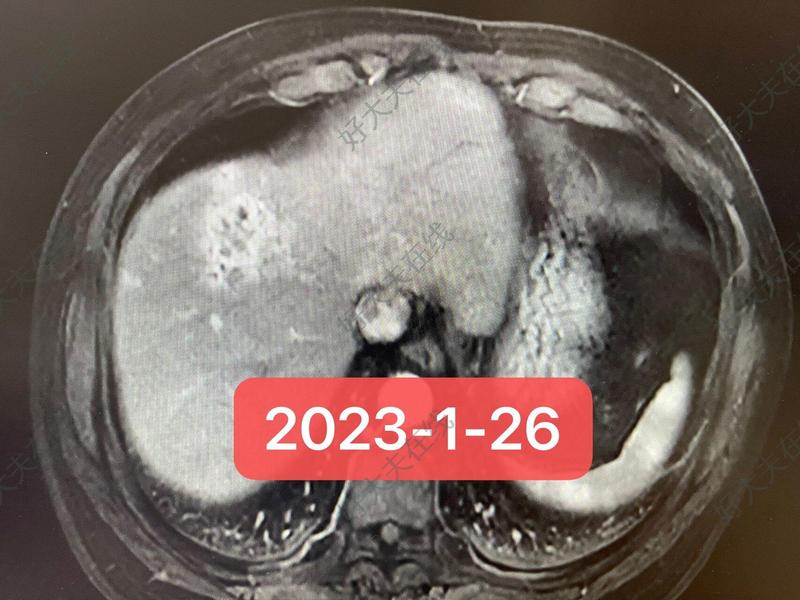

患者2022年10月發(fā)現(xiàn)右肝占位,緊密包繞下腔靜脈,CA199為546.9U/ml,經(jīng)肝穿刺確診為肝內(nèi)膽管細(xì)胞癌。后應(yīng)用GP+PD1單抗方案治療9療程,2023年5月評(píng)估腫瘤明顯縮小、與下腔靜脈界線較前明顯改善,CA199降至45.2U/ml?;颊呓?jīng)化療聯(lián)合免疫治療9次后,腫瘤指標(biāo)下降至趨于正常水平,影像學(xué)提示腫瘤明顯縮小、活性降低,但仍有270度包繞下腔靜脈?;颊呦乱徊皆撊绾沃委熌兀课铱紤]有以下選擇:1、原方案治療效果顯著、接近CR,繼續(xù)給予原方案治療;2、患者已行GP+PD1單抗方案治療9次,考慮化療毒副反應(yīng),調(diào)整為較弱化療方案+PD1單抗維持治療;3、PD1單抗單藥維持治療;4、患者腫瘤指標(biāo)顯著下降,腫瘤較前明顯退縮,考慮腫瘤大部分壞死,雖然仍包繞下腔靜脈、手術(shù)切緣難保證,結(jié)合腫瘤可能已大部分壞死,若左肝體積足夠,仍可行手術(shù)切除,術(shù)后再行輔助治療……經(jīng)完善PET-CT、三維重建、肝腎功能評(píng)估、MDT討論,并與患者及家屬充分溝通后,決定行擴(kuò)大右半肝切除術(shù)。術(shù)前影響及術(shù)后病理結(jié)果如下。歡迎討論并建議:1、手術(shù)能否給此類患者帶來(lái)生存獲益?(手術(shù)的必要性);2、若不手術(shù),該如何調(diào)整治療方案?何時(shí)停藥?3、術(shù)后輔助治療方案該如何選擇?4、術(shù)后輔助治療需要維持多長(zhǎng)時(shí)間?2022年10月2023年4月2023年4月術(shù)前術(shù)前術(shù)前術(shù)前CA199變化趨勢(shì)術(shù)后23個(gè)月2025-4-15日隨訪,患者狀態(tài)好、仍未復(fù)發(fā),處于無(wú)瘤生存狀態(tài)。